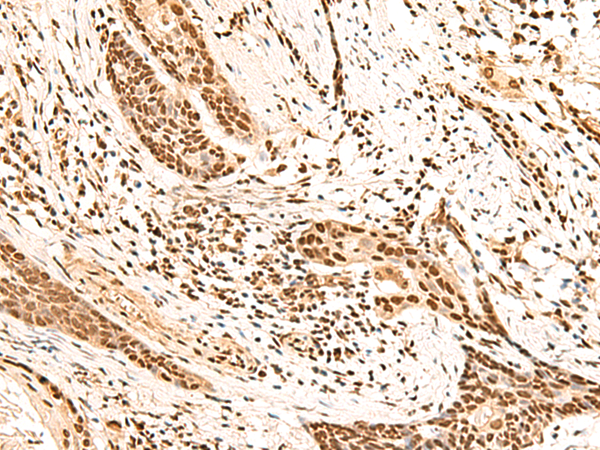

| IHC | 1/100-1/500 | Human,Mouse,Rat |

This antibody is commonly used in research applications like Western blotting, immunohistochemistry, and immunofluorescence to study SLIT1 expression and localization in tissues, particularly in the brain. It helps investigate SLIT1's involvement in neurodevelopmental disorders, cancer progression (due to its tumor-suppressive roles), and vascular remodeling. Species reactivity typically includes human, mouse, and rat samples.